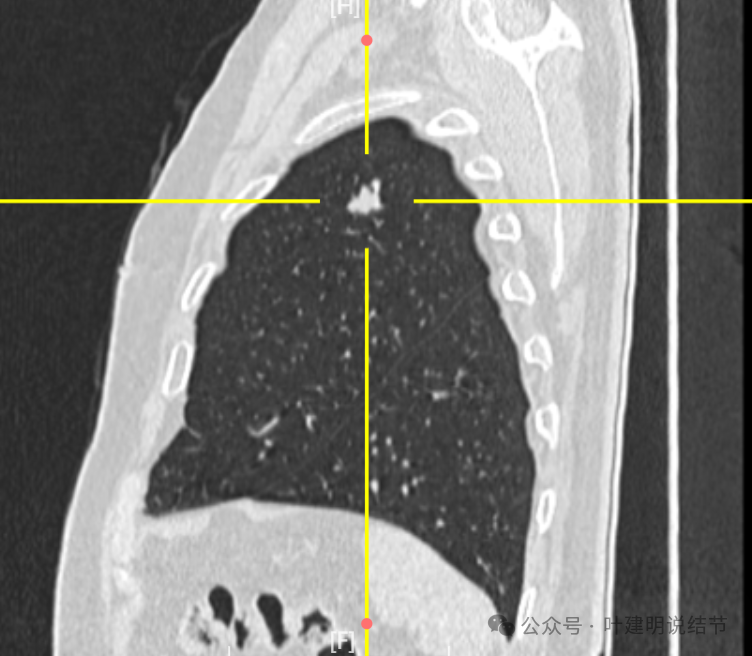

矢状位更显得形态不规则,表面不平,有浅分叶征。

我想我们这样来考虑问题:1、左肺上叶主病灶实性密度、随访持续进展,边缘有血管穿过并形成血管弯征,这种病灶要警惕是恶性的;2、位置在胸膜比较近的地方,单孔胸腔镜下局部切除方便,即便真的是肉芽肿性炎或者良性,手术创伤以及切除的肺组织并不多,但是却可以去除病灶并明确诊断;你赌他是良性,但如果事实上是恶性,实性密度的随访会延误病情。而切除即便良性也是利大于弊;3、左肺上叶这个病灶本身没有结核的典型表现,整体轮廓比较清楚,没有卫星灶,也没有边缘偏模糊的情况,影像上并不是很考虑是结核或者是肉芽肿性炎。虽然肉芽肿性炎也确实有随访进展的,但我们要从风险高低的角度来考虑;4、右侧腔静脉旁以及龙头下都有肿大淋巴结,左侧主动脉弓下也有肿大淋巴结。当时左肺上叶病灶非常微小的时候,淋巴结肿大已经存在。而且对比淋巴结没有进一步增大,左侧这个病灶却持续进展。这用一元论不能够解释,如果淋巴结肿大是反应性增生或者肉芽肿性炎症,和左侧主病灶是肿瘤性质的,那么就非常能够解释这样的现象。所以你这个病灶我的意见是建议胸腔镜下微创切除。先做楔形切除,如果良性结束手术,如果恶性可以考虑淋巴结采样,但个人并不主张一定要肺叶切除。我的截图上面蓝色箭头标注的是纵隔肿大的淋巴结,红色框起来的是左肺上叶主病灶不同时间段的样子。意见供参考!